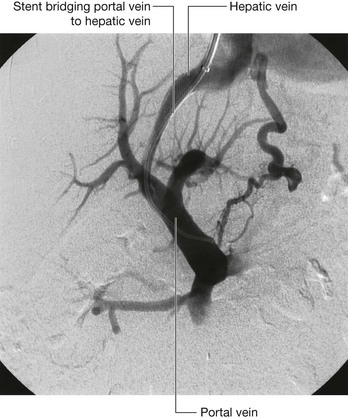

Urinary tract cancer

Most tumors that arise in the kidney are renal cell carcinomas. These tumors develop from the proximal tubular epithelium. Approximately 5% of tumors within the kidney are transitional cell tumors, which arise from the urothelium of the renal pelvis. Most patients typically have blood in the urine (hematuria), pain in the infrascapular region (loin), and a mass.

Renal cell tumors are unusual because not only do they grow outward from the kidney, invading the fat and fascia, but they also spread into the renal vein. This venous extension is rare for any other type of tumor, so, when seen, renal cell carcinoma should be suspected. In addition, the tumor may spread along the renal vein and into the inferior vena cava, and in rare cases can grow into the right atrium across the tricuspid valve and into the pulmonary artery (Figs. 4.142 and 4.143).

image

Fig. 4.142 Tumor in the right kidney growing toward, and possibly invading, the duodenum. Computed tomogram in the axial plane.

Fig. 4.143 Tumor in the right kidney spreading into the right renal vein. Computed tomogram in the axial plane.

Treatment for most renal cancers is surgical removal, even when metastatic spread is present, because some patients show regression of metastases.